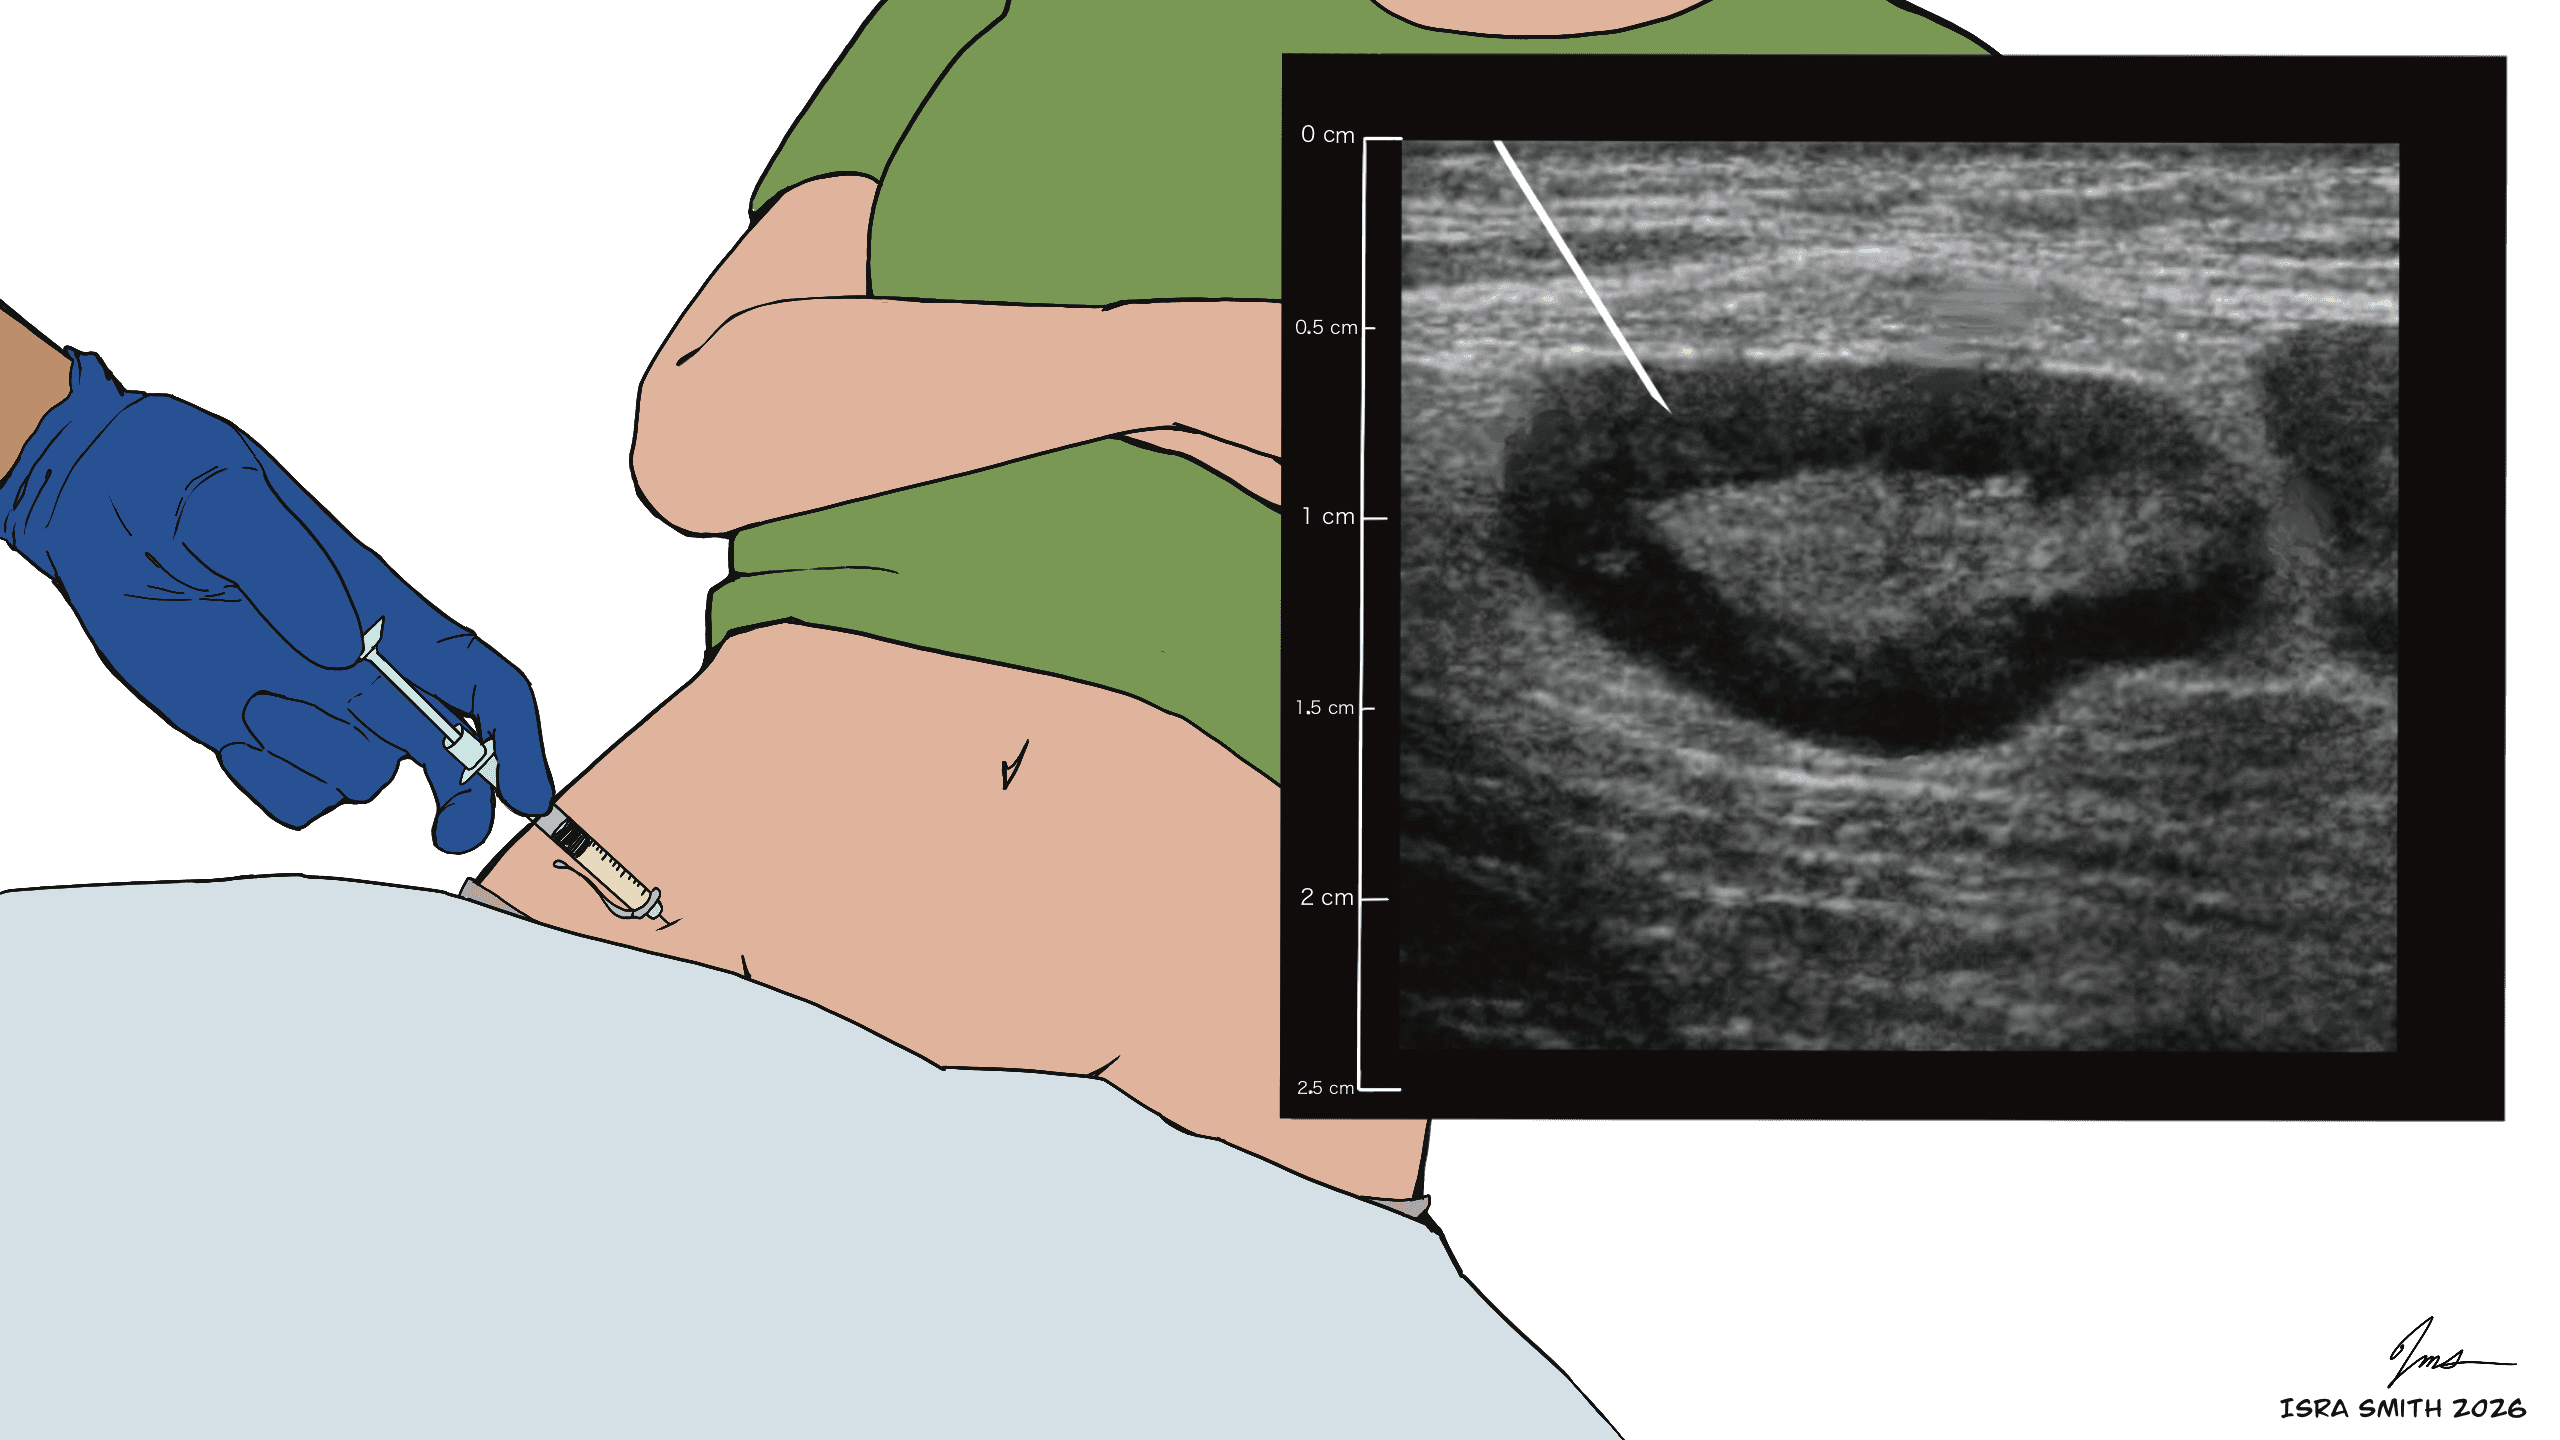

These images illustrate how ultrasound is used during ILIT to locate superficial lymph nodes and guide accurate allergen delivery during treatment.

Yes. ILIT uses low doses of allergen extract, and real-time ultrasound guidance ensures precise placement inside the lymph node. Most patients experience only mild, temporary soreness at the injection site.